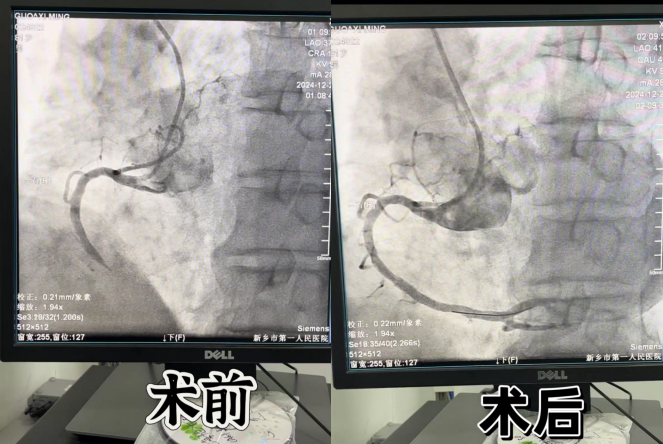

急性心肌梗死是心血管内科一个常见疾病,但同样也是心内科的急危重症。立即和家属进行沟通取得同意后,杨涛主任、郑明修副主任、睢国鑫医生立即为患者开辟绿色通道行急诊手术,术中冠状动脉造影提示:右冠中段100%闭塞,与家属沟通获得同意后行支架植入术,开通右冠,心电图ST段明显回落,患者胸闷症状也较前明显好转,术后安返病房。